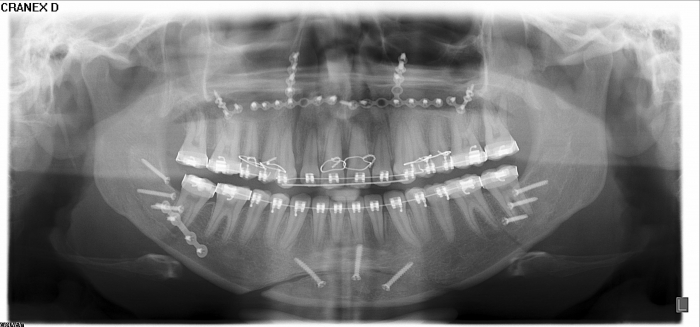

Raio - x após a cirurgia realizada em 2016 - Clínica Cliniface

Raio - x após a cirurgia realizada em 2016